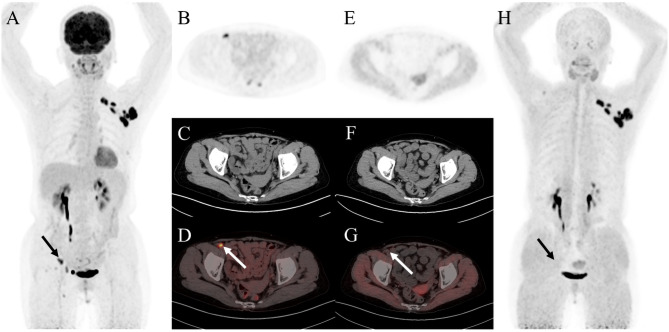

{"title":"Head-to-head comparison of <sup>18</sup>F-FDG and <sup>68</sup>Ga-FAPI PET/CT in common gynecological malignancies.","authors":"Tengfei Li, Jintao Zhang, Yuanzhuo Yan, Yue Zhang, Wenjie Pei, Qingchu Hua, Yue Chen","doi":"10.1186/s40644-025-00843-7","DOIUrl":null,"url":null,"abstract":"<p><strong>Background: </strong><sup>68</sup>Ga-FAPI (fibroblast activation protein inhibitor) is a novel and highly promising radiotracer for PET/CT imaging. It has shown significant tumor uptake and high sensitivity in lesion detection across a range of cancer types. We aimed to compare the diagnostic value of <sup>68</sup>Ga-FAPI and <sup>18</sup>F-FDG PET/CT in common gynecological malignancies.</p><p><strong>Methods: </strong>This retrospective study included 35 patients diagnosed with common gynecological tumors, including breast cancer, ovarian cancer, and cervical cancer. Among the 35 patients, 27 underwent PET/CT for the initial assessment of tumors, while 8 were assessed for recurrence detection. The median and range of tumor size and maximum standardized uptake values (SUV<sub>max</sub>) were calculated.</p><p><strong>Results: </strong>Thirty-five patients (median age, 57 years [interquartile range], 51-65 years) were evaluated. In treatment-naive patients (n = 27), <sup>68</sup>Ga-FAPI PET/CT led to upstaging of the clinical TNM stage in five (19%) patients compared with <sup>18</sup>F-FDG PET/CT. No significant difference in tracer uptake was observed between <sup>18</sup>F-FDG and <sup>68</sup>Ga-FAPI for primary lesions: breast cancer (7.2 vs. 4.9, P = 0.086), ovarian cancer (16.3 vs. 15.7, P = 0.345), and cervical cancer (18.3 vs. 17.1, P = 0.703). For involved lymph nodes, <sup>68</sup>Ga-FAPI PET/CT demonstrated a higher SUV<sub>max</sub> for breast cancer (9.9 vs. 6.1, P = 0.007) and cervical cancer (6.3 vs. 4.8, P = 0.048), while no significant difference was noted for ovarian cancer (7.0 vs. 5.9, P = 0.179). Furthermore, <sup>68</sup>Ga-FAPI PET/CT demonstrated higher specificity and accuracy compared to <sup>18</sup>F-FDG PET/CT for detecting metastatic lymph nodes (100% vs. 66%, P < 0.001; 94% vs. 80%, P < 0.001). In contrast, sensitivity did not differ significantly (97% vs. 86%, P = 0.125). For most distant metastases, <sup>68</sup>Ga-FAPI exhibited a higher SUV<sub>max</sub> than <sup>18</sup>F-FDG in bone metastases (12.9 vs. 4.9, P = 0.036).</p><p><strong>Conclusions: </strong><sup>68</sup>Ga-FAPI PET/CT demonstrated higher tracer uptake and was superior to <sup>18</sup>F-FDG PET/CT in detecting primary and metastatic lesions in patients with common gynecological malignancies.</p><p><strong>Trial registration: </strong>ChiCTR, ChiCTR2100044131. Registered 10 October 2022, https://www.chictr.org.cn , ChiCTR2100044131.</p>","PeriodicalId":9548,"journal":{"name":"Cancer Imaging","volume":"25 1","pages":"21"},"PeriodicalIF":3.5000,"publicationDate":"2025-02-28","publicationTypes":"Journal Article","fieldsOfStudy":null,"isOpenAccess":false,"openAccessPdf":"https://www.ncbi.nlm.nih.gov/pmc/articles/PMC11869701/pdf/","citationCount":"0","resultStr":null,"platform":"Semanticscholar","paperid":null,"PeriodicalName":"Cancer Imaging","FirstCategoryId":"3","ListUrlMain":"https://doi.org/10.1186/s40644-025-00843-7","RegionNum":2,"RegionCategory":"医学","ArticlePicture":[],"TitleCN":null,"AbstractTextCN":null,"PMCID":null,"EPubDate":"","PubModel":"","JCR":"Q2","JCRName":"ONCOLOGY","Score":null,"Total":0}

Results: Thirty-five patients (median age, 57 years [interquartile range], 51-65 years) were evaluated. In treatment-naive patients (n = 27), 68Ga-FAPI PET/CT led to upstaging of the clinical TNM stage in five (19%) patients compared with 18F-FDG PET/CT. No significant difference in tracer uptake was observed between 18F-FDG and 68Ga-FAPI for primary lesions: breast cancer (7.2 vs. 4.9, P = 0.086), ovarian cancer (16.3 vs. 15.7, P = 0.345), and cervical cancer (18.3 vs. 17.1, P = 0.703). For involved lymph nodes, 68Ga-FAPI PET/CT demonstrated a higher SUVmax for breast cancer (9.9 vs. 6.1, P = 0.007) and cervical cancer (6.3 vs. 4.8, P = 0.048), while no significant difference was noted for ovarian cancer (7.0 vs. 5.9, P = 0.179). Furthermore, 68Ga-FAPI PET/CT demonstrated higher specificity and accuracy compared to 18F-FDG PET/CT for detecting metastatic lymph nodes (100% vs. 66%, P < 0.001; 94% vs. 80%, P < 0.001). In contrast, sensitivity did not differ significantly (97% vs. 86%, P = 0.125). For most distant metastases, 68Ga-FAPI exhibited a higher SUVmax than 18F-FDG in bone metastases (12.9 vs. 4.9, P = 0.036).